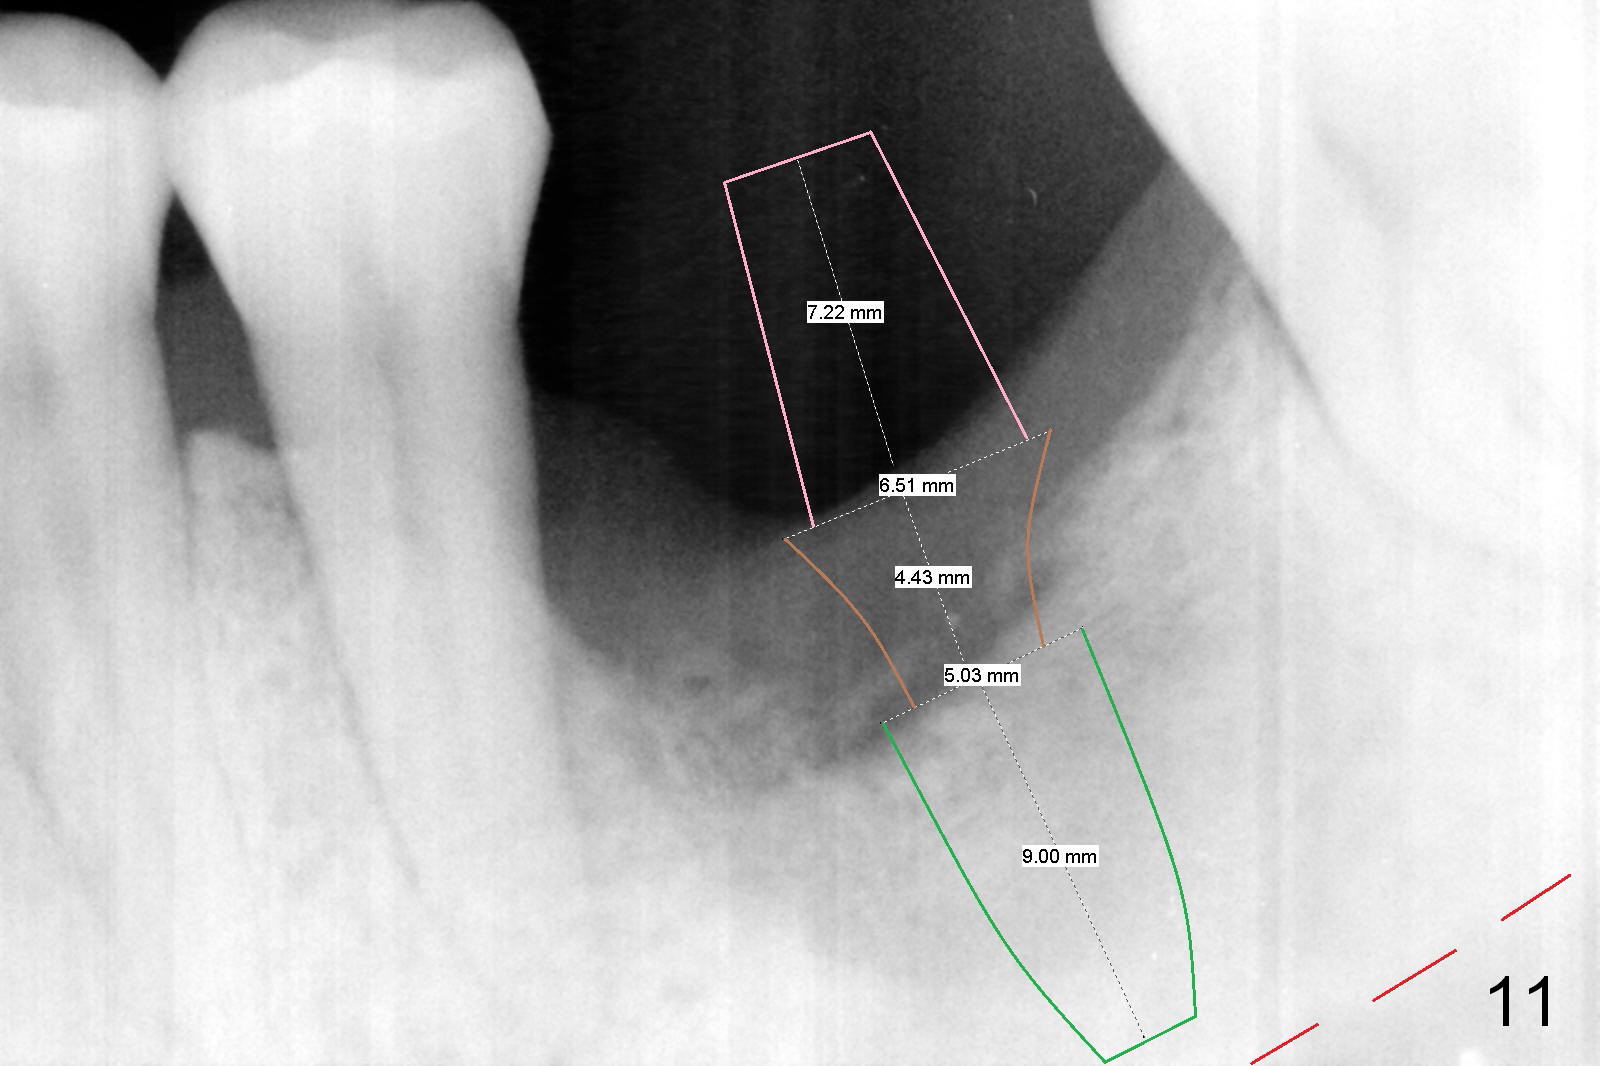

Considering the severe bone loss in the meisal socket, socket preservation is indicated if immediate implant is not feasible.  Preop exam shows that the mesiobuccal gingival recession (Fig.1 MB) is not as severe as the mesiolingual one (Fig.2 ML).  Because of oozing from the mesial socket, buccal envelop incision is made with flap raising to increase visibility.  Probably due to periodontal infection, pain control is difficult.  Osteotomy buccal to the Inferior Alveolar Canal proves to be risky.  In addition, osteotomy in the mesial socket is more difficult than the distal one (Fig.3).  Once the osteotomy depth is determined relative to the superior border of the Inferior Alveolar Canal (4 mm), the osteotomy depth increases by 2 mm.  A 5.5x10 mm implant is placed with insertion torque ~ 35 Ncm (Fig.4); a 15 ° angled abutment (5.5 mm in diameter, 4 mm in cuff) is placed mesially.  Then the abutment is turned lingually favorable for restoration (Fig.5), the remaining socket is filled with allograft/Osteogen (*) and Collagen Plug.

There is bone growth in the mesial socket 5 months post graft (Fig.10).  Use Magic Split to get access and test bone density (which must be low or medium in the upper portion).  Use drills beyond the socket if necessary.  Crown/implant ratio is unfavorable (Fig.11); so progressive loading is essential.